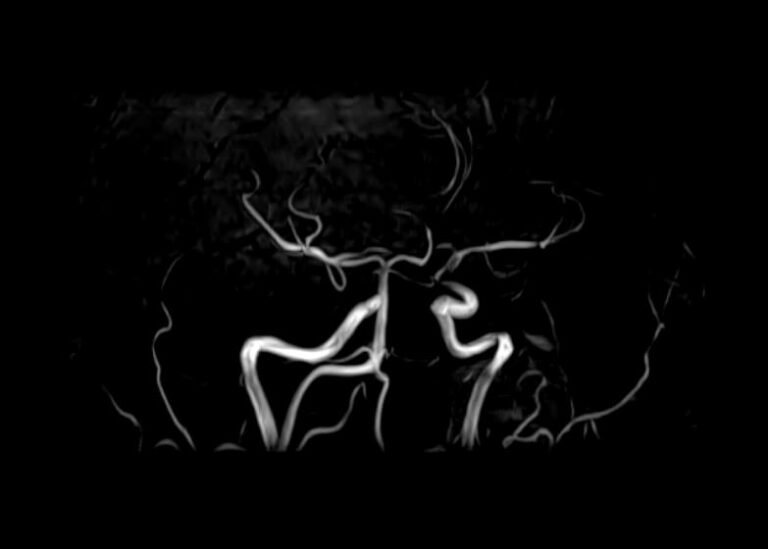

МР-ангиография — неинвазивный безопасный метод исследования для диагностики патологии сосудистой системы головы и шеи. Магнитно-резонансная ангиография позволяет получить трехмерное изображение кровеносных сосудов, оценить анатомическое строение сосудистой системы головного мозга и функциональные особенности кровотока.

С помощью электромагнитных волн томограф послойно сканирует структуры исследуемого органа, затем посредством компьютерных программ преобразует полученные данные в трехмерное изображение. При этом на снимке видна только сосудистая система без окружающих тканей. Таким образом, сканирование в режиме ангиографии позволяет визуализировать артерии и вены головного мозга без контрастирования. Однако в некоторых случаях для более точной диагностики может потребоваться введение контраста. Для этого используются гадолиний содержащие контрастные вещества. Дополнительное контрастирование дает возможность визуализировать мельчайшие сосуды и выявить нарушения микроциркуляции головного мозга.